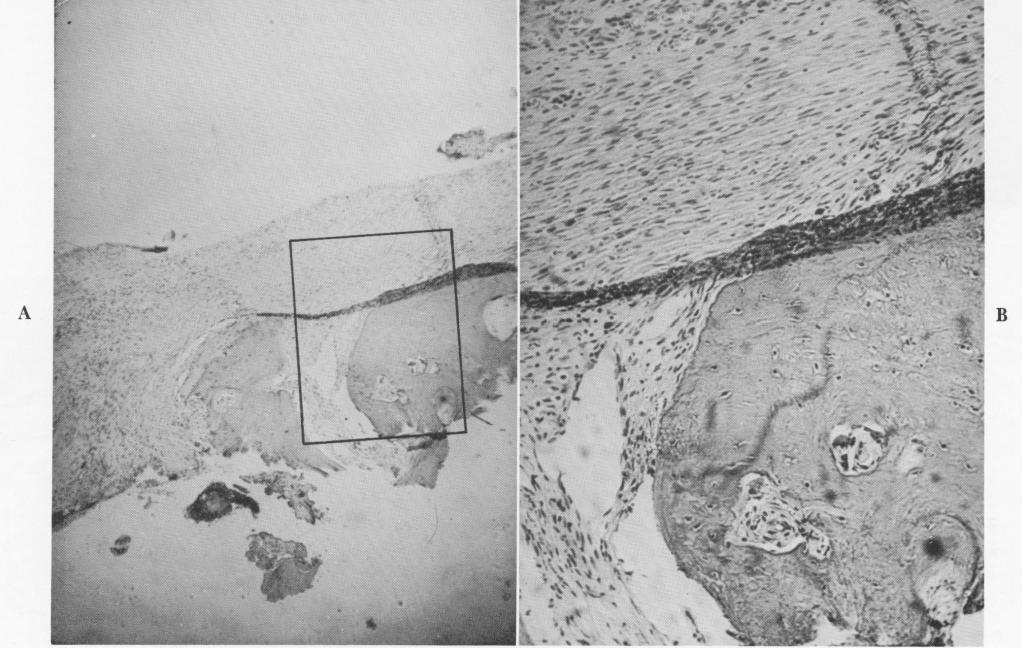

Fig. 4-71. A, Section through the tissue found embedded in the vent of a vent-plant. Under low power both fibrous tissue and bone are evident. B, A high-power view reveals the healthy nature of the bone inside the vent, as evidenced by the osteocytes. (Courtesy K. R. Blakey, Howard University.)

1 Fibrous tissue and bone are seen in vent of vent plant implant